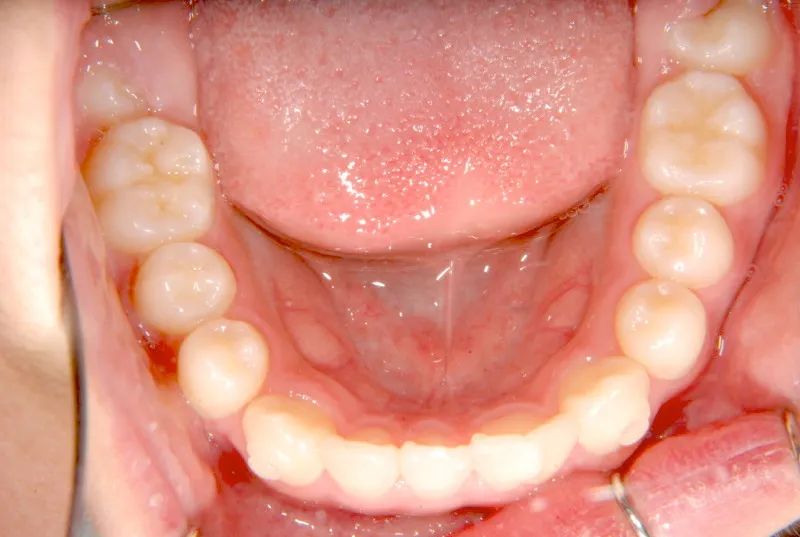

上下の歯並びが狭く、永久歯の生える隙間がありません。

右下に癒合歯があり 上下の歯並びのアーチが悪くなっています。

オリジナルの着け外しのできる装置で治療しました。

治療回数○回、4年7ヶ月の治療期間で矯正治療を終了しました。

1期治療で十分な結果が得られたと思います。